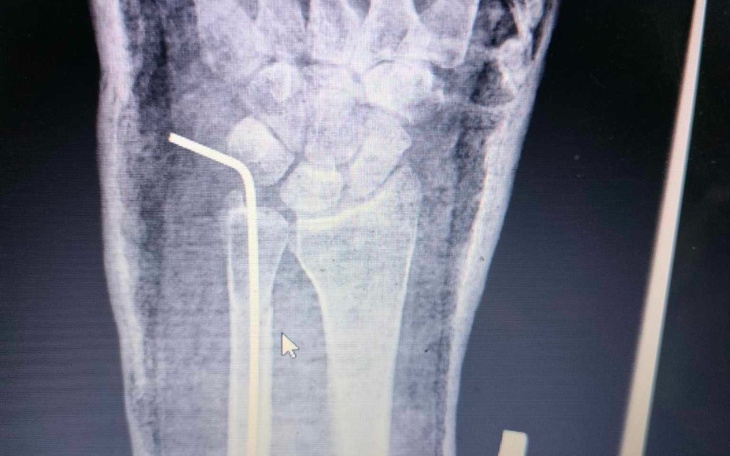

Przyszedł ortopeda, o nazwisku jak moje panieńskie co trochę mnie uspokoiło, poinformował mnie że doszło do złamania kości łokciowej z niedopuszczalnym odchyleniem i konieczna jest operacja.

Okazało się że nie mieli odpowiednich blaszek i umieścili mi drut, na to gips.

6 długich tygodni w gipsie, który co drugi dzień muszę otwierać, zmieniać opatrunek przy drucie i zawijać na nowo. Później zdjęcie kontrolne, decyzja kiedy usunięcie drutu i rehabilitacja.